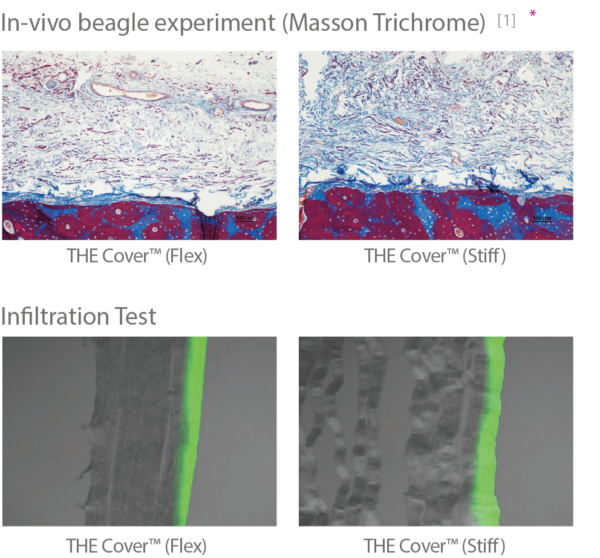

- THE Cover™ (Flex / Stiff) — membrane resorbabile din colagen tip I (origine porcină). Flex pentru adaptare facilă pe contururi neregulate; Stiff pentru menținerea spațiului și protecția grefei când este necesară rigiditate mai mare.